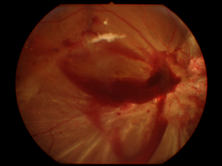

视网膜脱离

视网膜脱离是一种常见的糖尿病视网膜病变晚期严重并发症,可对患者造成显著的视力损伤。

糖尿病视网膜病变引起的视网膜脱离总是伴随“纤维-血管组织”的牵引。

在患者身体情况允许的情况下,应进行手术治疗。

▲ 视网膜脱离

▲ 视网膜前出血(PRH)可见于视网膜脱离的表面。